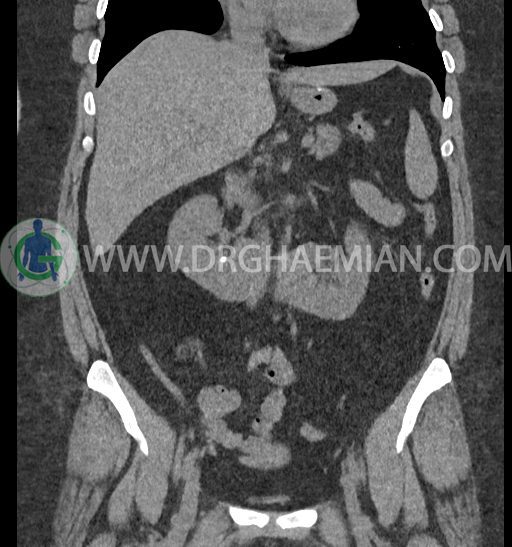

سی تی اسکن شکم و لگن با استفاده از اشعات ایکس تصاویر عرضی از ناحیه شکم و لگن ایجاد میکند. در این کیس کلیه نعل اسبی و سنگ کلیه مشاهده می شود.

در سی تی اسکن اسپیرال شکم و لگن بدون کنتراست (مولتی دیدکتور 16 با مقاطع ظریف و بازسازی های ساژیتال و کرونال) :

-horseshoe kidney

-حداقل سه سنگ 5mm در کلیه راست و یک سنگ 3mm در کلیه چپ بدون شواهدی از هیدرونفروز